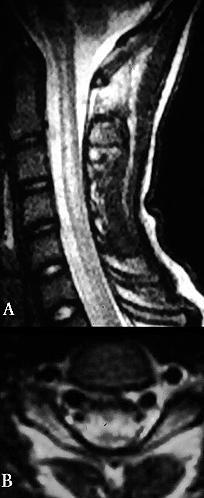

Estes dados implicam que o mergulho pode produzir danos subclínicos ao cérebro, medula espinhal (Fig. 2, 3), ouvido interno, retina e pequenas vias aéreas do pulmão. Outros estudos sugerem diminuição significativa das funções pulmonares e cognitivas.

A ressonância magnética (MRI) deu aos investigadores uma ferramenta adicional para estudar o sistema nervoso central em mergulhadores. Com a ressonância magnética, foi relatada alta intensidade de sinal (pontos brilhantes), indicando danos nos tecidos, em mergulhadores e acredita-se que tenha grande potencial para identificar danos causados ao SNC.

Foi usado pela primeira vez pelos noruegueses (Todnem e associados) para estudar doenças descompressivas, e eles descobriram que até 33% de todos os mergulhadores apresentavam alterações de alta intensidade de sinal. Estudos semelhantes realizados por Brubakk e Rinck e colaboradores confirmaram essas descobertas.